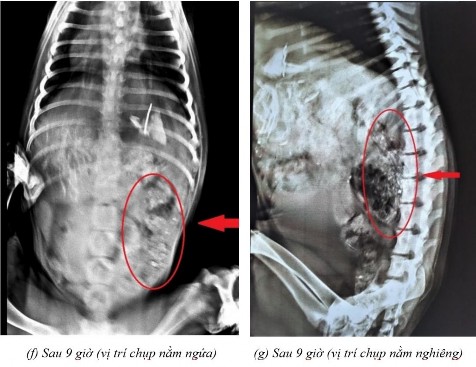

Phụ lục 5.4. Hình ảnh X-quang chó 5 ở thời điểm (a) sau 2 giờ 20 ở vị trí nằm nghiêng, (b) sau 4 giờ ở vị trí nằm ngửa, (c) sau 4 giờ ở vị trí nằm nghiêng, (d) sau 7 giờ ở vị trí nằm ngửa, (e) sau 7 giờ ở vị trí nằm nghiêng, (f) sau 9 giờ ở vị trí nằm ngửa, (g) sau 9 giờ ở vị trí nằm nghiêng, (h) sau 11 giờ 40 ở vị trí nằm ngửa và (i) sau 11 giờ 40 ở vị trí nằm nghiêng